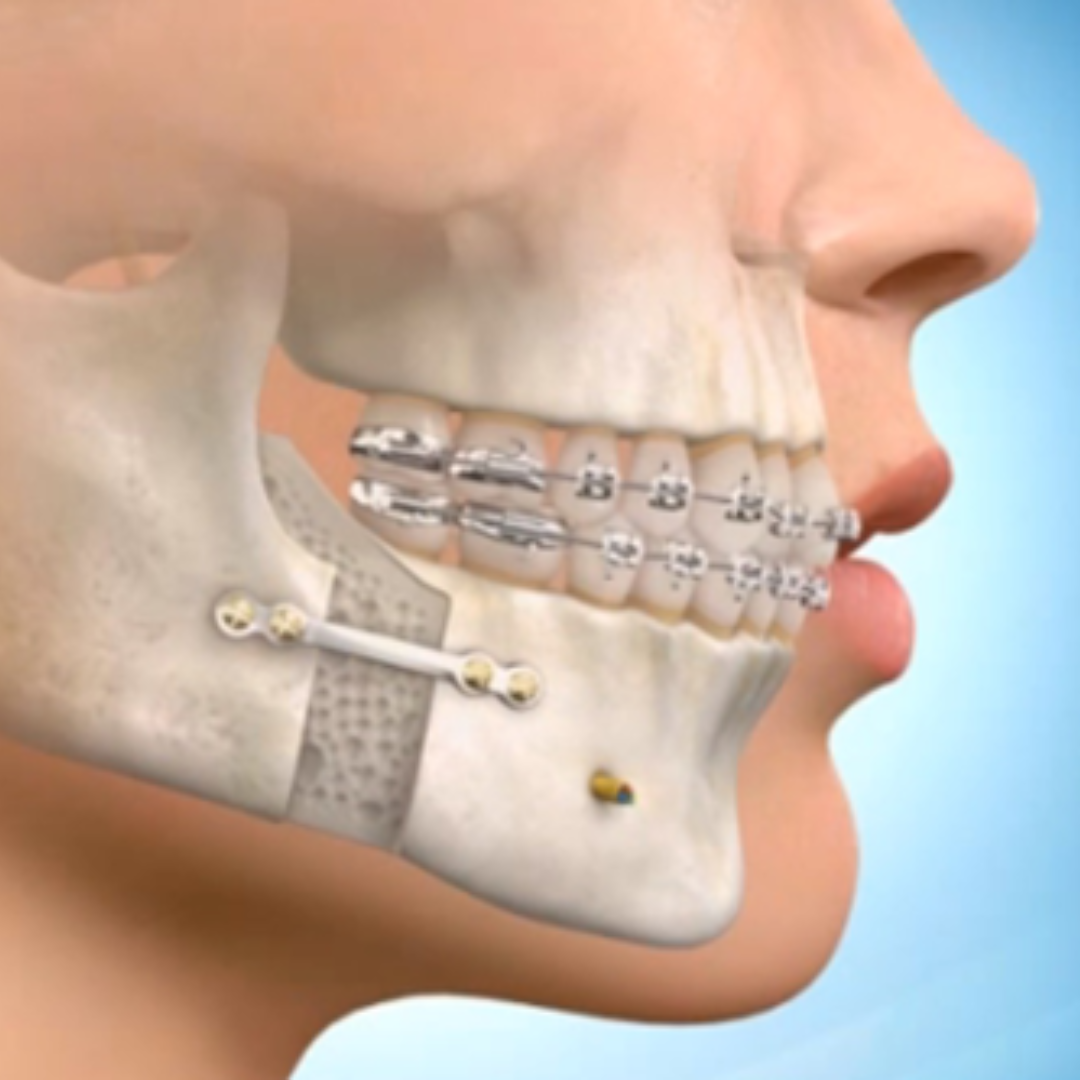

Orthognathic Surgery

“My bite was misaligned, and I always felt self-conscious about my jaw. After undergoing orthognathic surgery here, not only is my profile more balanced, but I can eat and speak more comfortably. The team at Aesthetic Plastic Surgery truly changed my life.”

“Aesthetic Plastic Surgery isn’t just about aesthetics—it’s about functionality too. I got both braces and corrective jaw surgery here, and the transformation has been incredible. I can finally smile wide without hesitation.”